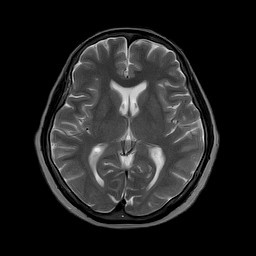

MRI検査は、間隔を空けずに検査しても体は大丈夫ですか?

MRIは磁力を利用する検査です。

放射線ではないので被爆の心配はなく、続けて検査しても身体に影響はないといわれています。